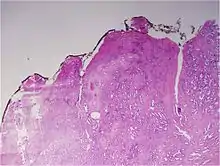

A pathologist microscopically examines the biopsy specimen for certain "Gleason" patterns. These Gleason patterns are associated with the following features:

- Pattern 1 - The cancerous prostate closely resembles normal prostate tissue. The glands are small, well-formed, and closely packed. This corresponds to a well differentiated carcinoma.

- Pattern 2 - The tissue still has well-formed glands, but they are larger and have more tissue between them, implying that the stroma has increased. This also corresponds to a moderately differentiated carcinoma.

- Pattern 3 - The tissue still has recognizable glands, but the cells are darker. At high magnification, some of these cells have left the glands and are beginning to invade the surrounding tissue or having an infiltrative pattern. This corresponds to a moderately differentiated carcinoma.

- Pattern 4 - The tissue has few recognizable glands. Many cells are invading the surrounding tissue in neoplastic clumps. This corresponds to a poorly differentiated carcinoma.

- Pattern 5 - The tissue does not have any or only a few recognizable glands. There are often just sheets of cells throughout the surrounding tissue. This corresponds to an anaplastic carcinoma.

In the present form of the Gleason system, prostate cancer of Gleason patterns 1 and 2 are rarely seen. Gleason pattern 3 is by far the most common.

The Gleason grade is based on tissue architectural patterns rather than purely cytological changes. These tissue patterns are classified into 5 grades, numbered 1 though 5. Lower numbers indicate more differentiation, with pattern 5 being the least differentiated.[4][7] Differentiation is the degree to which the tissue, in this case the tumor, resembles native tissue. Greater resemblance (lower grade) is typically associated with a better prognosis.